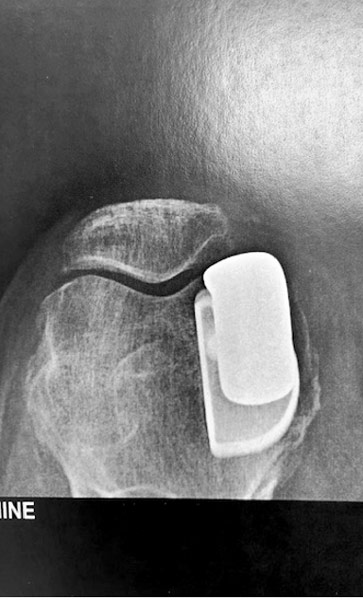

Arthrose externe de rotule isolée chez une patiente jeune, âgée de 45 ans.